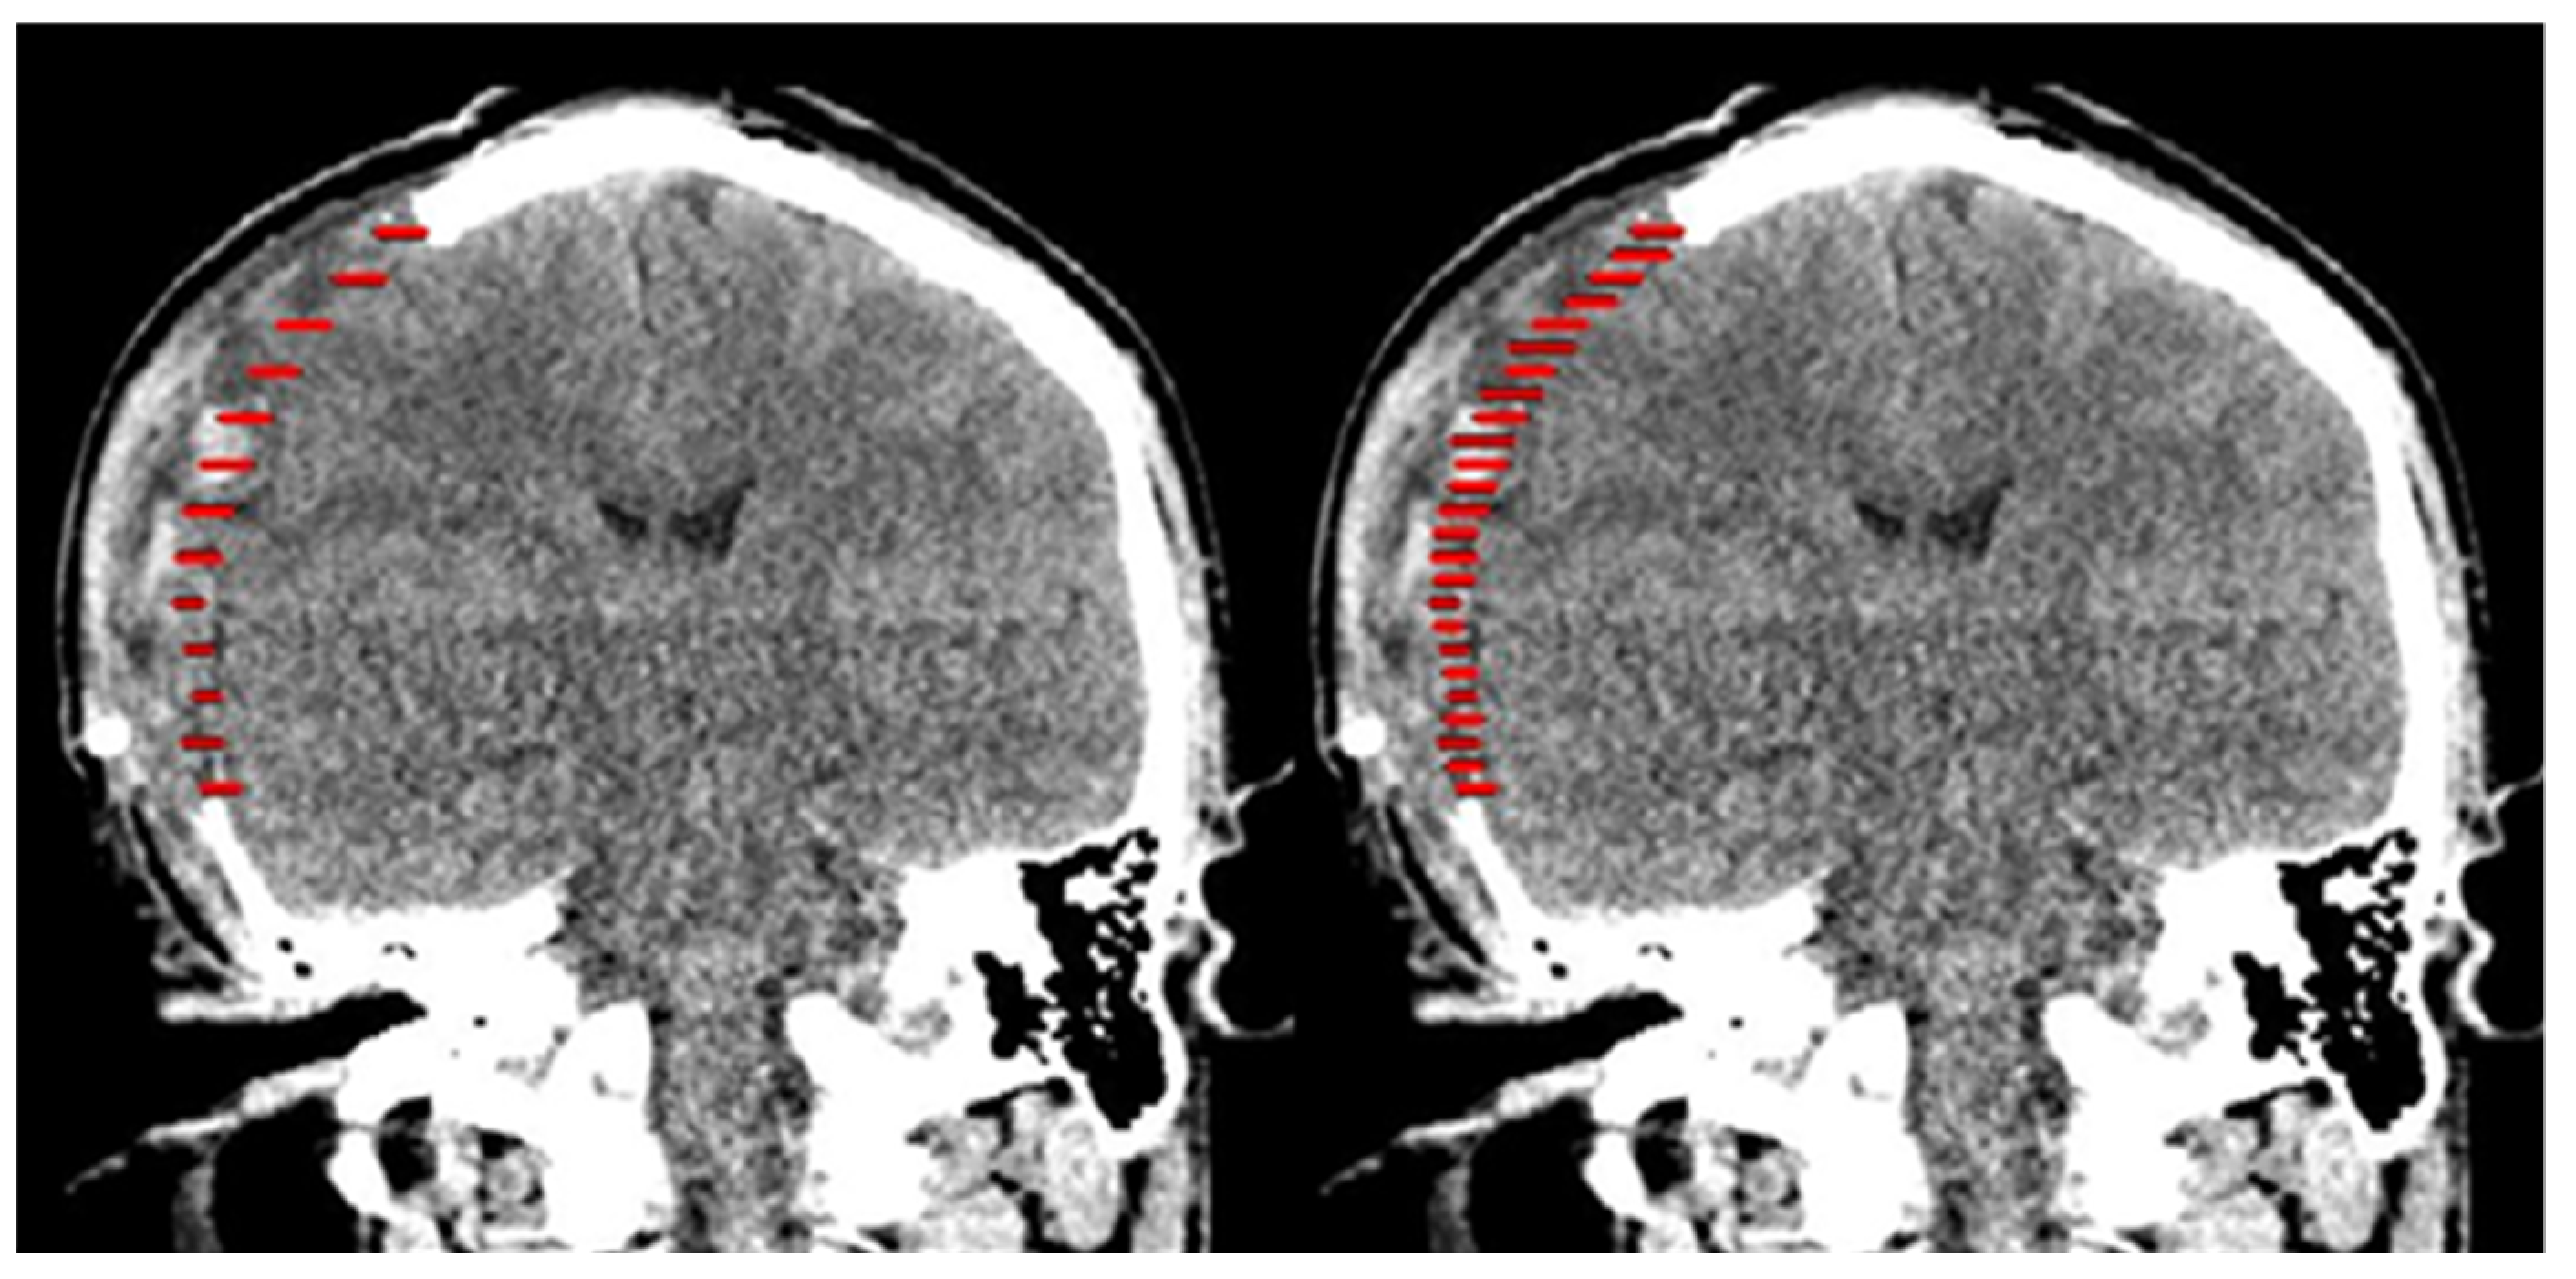

2.2. Design of Cranial Implants Using MITK Software